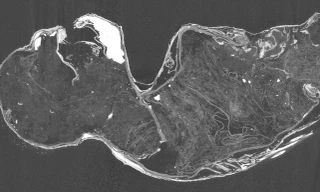

TPO - Người Ai Cập cổ đại đã phát triển một phương pháp phức tạp để bảo quản xác chết và đó chính là ướp xác. Quá trình này không chỉ thể hiện sự tỉ mỉ, mà còn ẩn chứa nhiều bí mật về tâm linh, tôn giáo của người Ai Cập cổ.

Sau khi băng hà, các pharaoh Ai Cập thời cổ đại được ướp xác để bảo tồn nguyên vẹn thi thể giúp linh hồn sang thế giới bên kia. Một trong những điểm gây chú ý là vị trí hai tay của xác ướp vô cùng quan trọng.

Người Ai Cập cổ đại thực hiện ướp xác người chết vì tin rằng làm như vậy thì người chết sẽ có cuộc sống vĩnh hằng ở thế giới bên kia. Do vậy, chỉ những người giàu có và quyền lực mới có đủ khả năng thực hiện việc ướp xác.